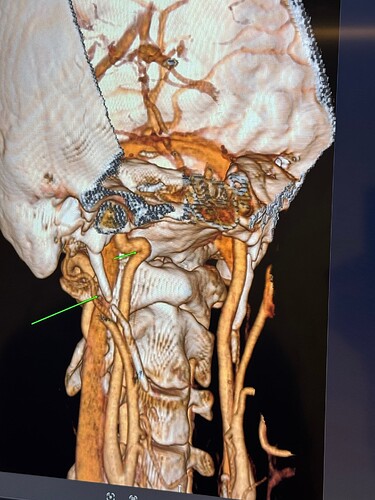

The IJVs do collapse naturally when flat, so it could be due to that, in your 3rd image it looks like the IJV is flattened higher up, so what would be right by the skull base. It could be like that naturally because of being flat for the CT, or it could be that it is being compressed where it emerges from the skull at the jugular foramen - if styloids are quite thick that is possible, & yours do look a little wide at the top… It looks like there could be something pinching the IJV between it & the styloid where you’ve marked too; we’ve had members who’ve had compression from an enlarged SCM muscle, the digastric muscle, omahyoid muscle, as well as other blood vessels & nerves… I’d guess where the compression is that the digastric muscle would be the most likely if it was a muscle, or maybe the stylohyoid muscle, although we don’t hear much about that one!

@Rob12345 - Welcome to our forum! I have nothing to add to what @Jules said, but did want to say WOW! You do have very long styloids. The “kink” in your ICA (internal carotid) isn’t really a kink more of a curve, but I can see based on the image, that it could be causing some slowed or backed up blood flow going into your brain. The IJV compression is curious as it appears to be more than the styloid causing the problem but clearly C1 seems not to be involved. I think Jules has made some logical assumptions regarding other possible compression culprits.

@Rob12345 - I can see you have bilateral IJV compression in the images you’ve posted & it’s possible the middle image in your first set of pictures is pointing to collateral veins. I’m not great at identifying collaterals, but I can say for sure your IJVs are being squashed between your styloids & C1.